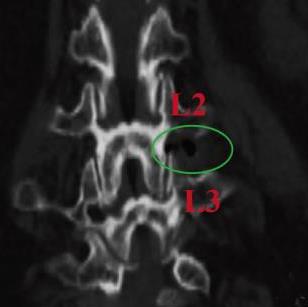

• 单通道非同轴脊柱内镜经椎间孔外入路(椎板外切迹)治疗极外侧椎间盘突出症的临床疗效观察

2026, 32(3):28-36. DOI: 10.12235/E20250050

摘要 (43) HTML (65) PDF 6.88 M (47) 评论 (0) 收藏

摘要:目的 观察单通道非同轴脊柱内镜经椎间孔外入路(椎板外切迹)治疗极外侧椎间盘突出症(FLLDH)的临床疗效。方法 回顾性分析2022年5月-2024年5月该院收治的,行单通道非同轴脊柱内镜经椎间孔外入路(椎板外切迹)治疗的FLLDH患者70例。于术前和术后,评估腰腿疼痛程度、腰椎功能和临床疗效。结果 相较于术前,术后3 d和3个月,患者下肢视觉模拟评分法(VAS)评分、腰部VAS评分、Oswestry功能障碍指数(ODI)、数字分级评分法(NRS)评分和Roland-Morris功能障碍问卷(RMDQ)评分明显降低,日本骨科协会(JOA)评分明显升高,差异均有统计学意义(P < 0.05);改良MacNab评分标准显示,末次随访时的优良率为94.28%。结论 单通道非同轴脊柱内镜经椎间孔外入路(椎板外切迹)治疗FLLDH,能明显改善患者腰腿疼痛和腰椎下肢功能,其具有创伤小、易操作、安全性高和疗效好等优点,值得在临床推广应用。